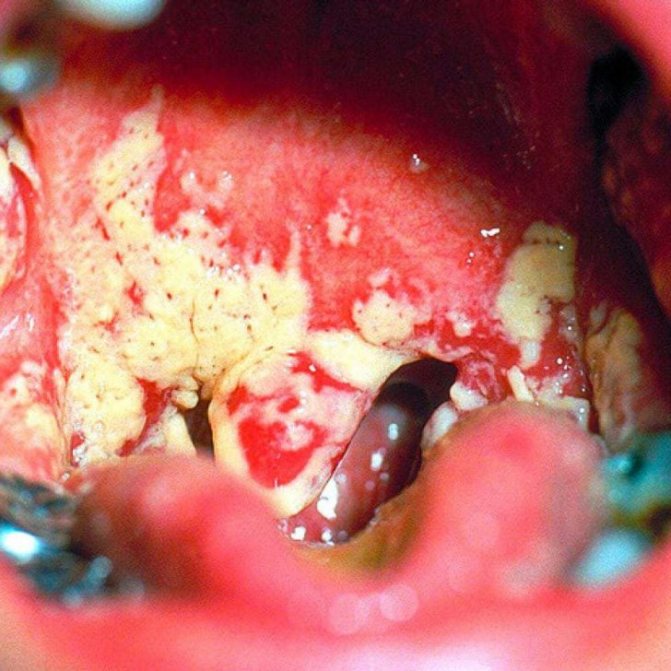

миндалины, пораженные фолликулярным тонзиллитом

Часто кажется, что гной, заключенный в фолликулах, можно легко снять с поверхности миндалины. Это не так. При попытке удаления гнойники не устраняются, ибо расположены под эпителием слизистой оболочки.

При фолликулярном тонзиллите гнойники не сливаются и размеры каждого не превышают 1-3 мм. То есть не формируется знаменитый белый надет на миндалинах.

Как выглядит фолликулярная ангина, и чем она отличается он лакунарной формы, можно увидеть на фото.

У детей и взрослых характерным является острое начало фолликулярной ангины (см. фото), в первые дни наиболее выражены общие симптомы: повышенная до 38-40 °C температура тела, лихорадка, потливость, боли во всем теле, плохой сон и аппетит, слабость. Вскоре пациента начинает беспокоить боль в горле, которая становится более интенсивной при глотании слюны и пищи, нередко иррадиирует в ухо. Нарастает болезненность регионарных лимфоузлов (углочелюстных, шейных). Осматривая глотку, можно заметить увеличенные в объеме, гиперемированные миндалины с просвечивающими сквозь эпителиальную ткань фолликулами, наполненными гнойным содержимым.